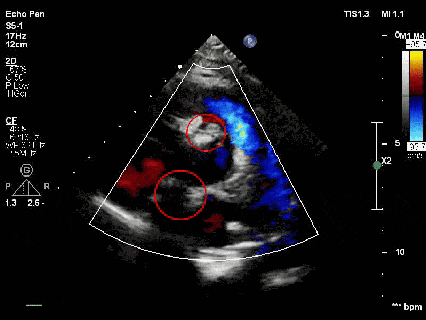

心脏超声:室间隔缺损(膜周部)、房间隔缺损(继发孔型)

术前TTE示:膜周部室间隔缺损,基底大小11.3×10.5mm,分流口大小3.6mm,左向右分流,峰值流速4.07m/s。

术前TTE示:房间隔缺损继发孔型,断端大小4.5-5mm,薄弱范围约10mm,左向右分流 。

释放前超声

释放前超声下封堵器型态良好,骑跨室间隔两侧

释放后超声

超声下可见室水平和房水平都无残余分流

心脏彩超:心脏超声下可见两个封堵器双盘稳固夹持,无残余分流;

术后1个月心脏超声,房室水平皆无残余分流